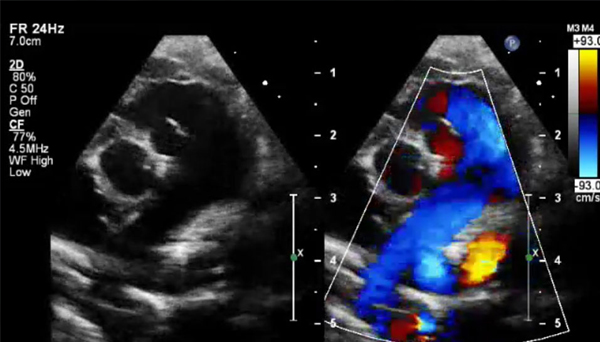

Pediatric echocardiography is a specialized form of heart ultrasound used to assess the structure and function of a child’s heart, from newborns to adolescents

This non-invasive test helps diagnose congenital heart defects, valve problems, and other cardiac issues in children. Using high-frequency sound waves, pediatric echocardiography provides real-time images, enabling cardiologists to closely monitor a child's heart health